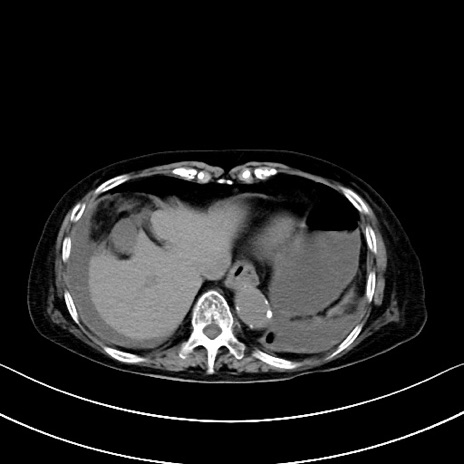

横断像

他院CT